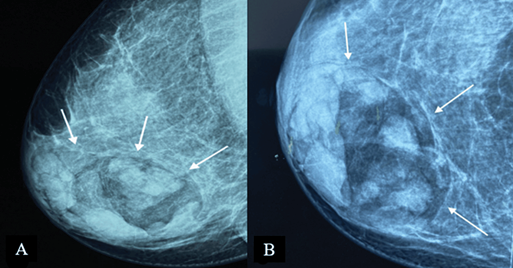

On mammography, MH is typically seen as an inhomogeneous oval or round formation, with radio-opaque and radiotransparent areas that reflect the presence of tissues of different densities (Figure 2). The lesion bears a thin, well-defined radiopaque border (pseudocapsule). The presence of different densities within the pseudocapsule tends to create a pathognomonic impression of a “slice of salami” [2, 25] or a bull’s eye [2] or a “breast within a breast” [26].

Figure 2. Digital mammography: medio-lateral oblique (A) and cranio-caudal (B) projections of the right breast – a large, well-defined mass containing radiolucent (fat) and radiopaque (soft tissue) densities can be seen. It is surrounded by a thin radiopaque capsule, presenting a “breast within a breast” appearance. Image credits: El Yousfi Z, El Mansoury FZ, El Bakkari A, Omor Y, Latib R. Breast hamartoma with synchronous contralateral breast cancer: a case report. Cureus 2024; 16(8): e66534. DOI: 10.7759/cureus.66534. Reused under the terms of the Creative Commons Attribution License CC-BY 4.0. (https://creativecommons.org/licenses/by/4.0/deed.en).